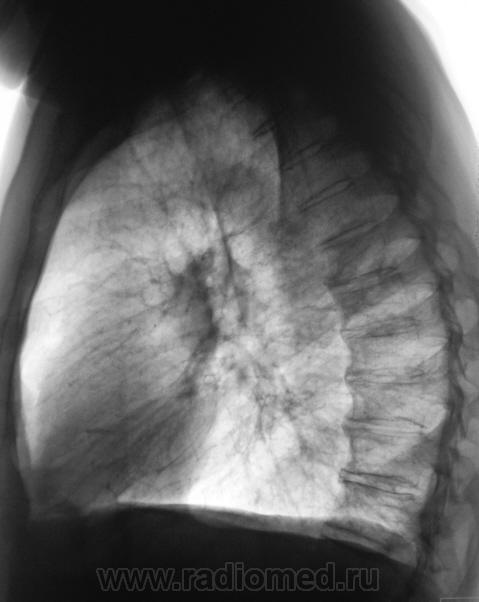

Первый срез.

Второй срез.

И..? Если Вы имеете в виду очаги, тень на ТБС мало похожа.

На верхушке похоже на свежие очаги.

А в каком сегменте по-Вашему расположена тень?

Возможно, я не совсем ясно выразился, но тень слева, та, что на рентгенограмме на уровне 3 ребра весьма похожа, и очень, на неопластический процесс.

"Подтекст", именно в том, что, кроме указанной тени, были обнаружены и очаги, генез которых не вызывает сомнения.